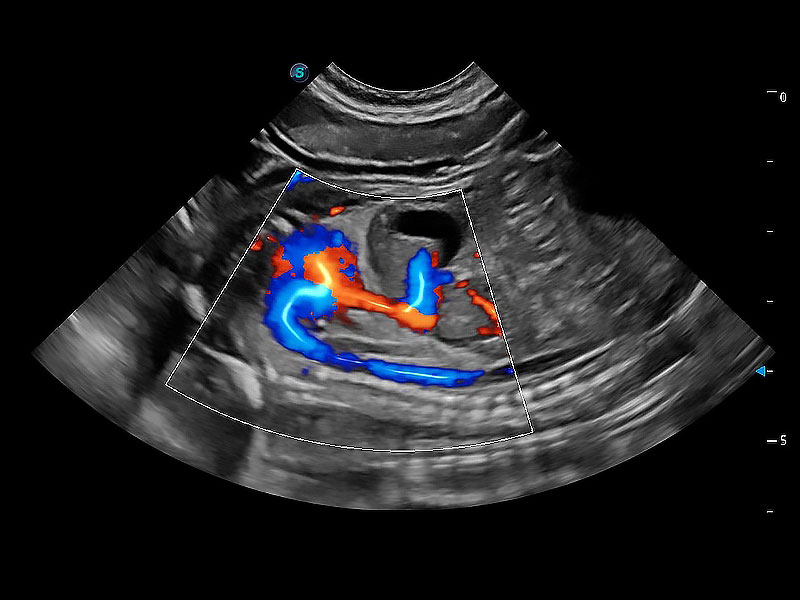

極大提升超低速微細(xì)血流的檢出能力,同時(shí)更精準(zhǔn)地濾除軟組織和超聲信號(hào),為獸用醫(yī)生提供以往無(wú)法通過(guò)常規(guī)血流獲得的疾病診斷信息。

在傳統(tǒng)二維血流成像的基礎(chǔ)上,呈現(xiàn)血流的立體感,具有動(dòng)感的生命力之美。即便是微小的血管也能輕松應(yīng)對(duì),提高了血流的視覺敏感性。